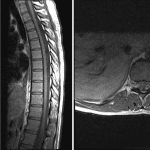

Indication: Endocarditis, rule out epidural abscess (unable to receive contrast)

Findings

- Prominent pulsation artifact in the dorsal subarachnoid space throughout the thoracic spine without discrete intradural or extradural collection

- Normal marrow signal and vertebral alignment

- Normal cord signal and contour

- No significant focal degenerative changes

- Multiple cavitary lesions in both lungs

Diagnosis

- CSF pulsation artifact

Prominent pulsation artifact in the dorsal subarachnoid space throughout the thoracic spine without discrete intradural or extradural collection. No significant mass effect on the thoracic spinal cord, which is normal in signal and contour.

No noncontrast MRI evidence of discitis/osteomyelitis.

Multiple cavitary lesions in both lungs, concerning for septic embolic disease in the setting of endocarditis. Recommend chest CT for further assessment.